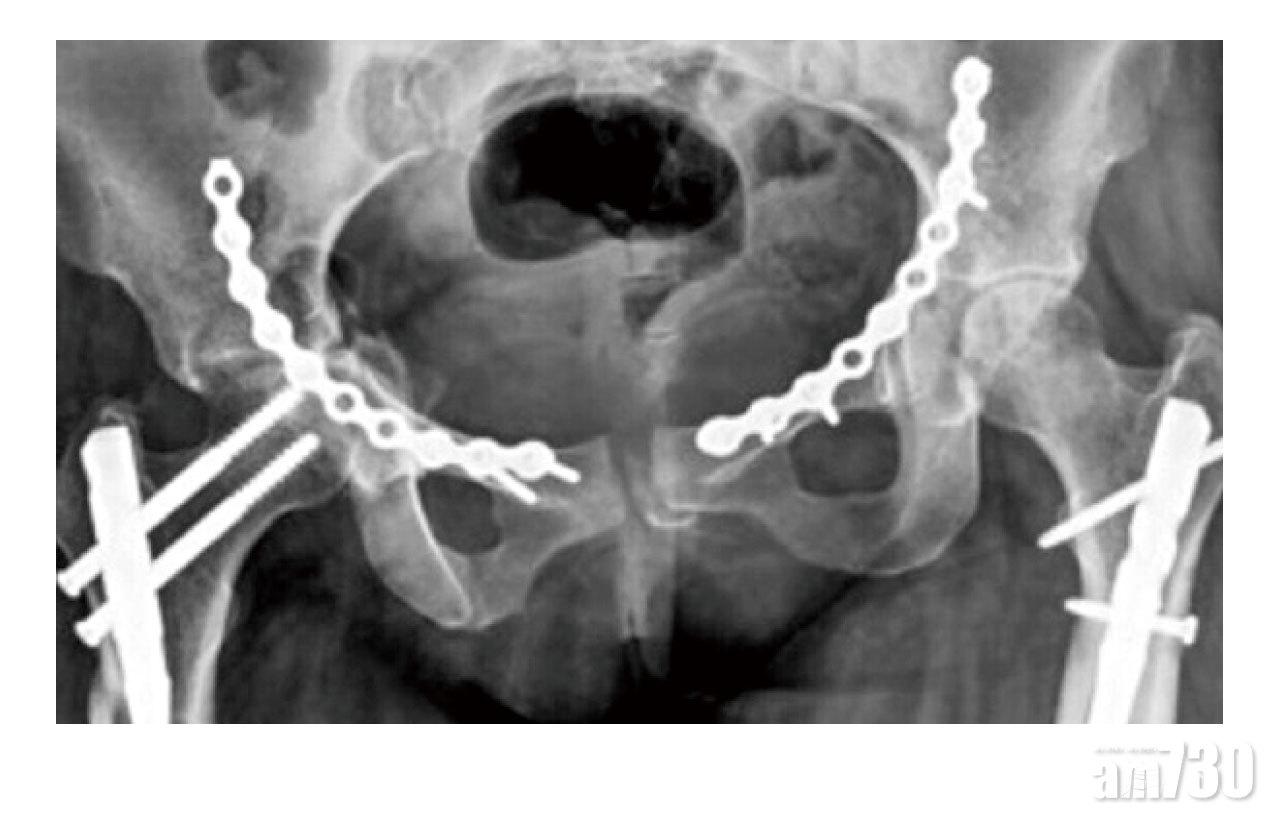

為減低這種術後併發的二次傷害(Second Hit Phenomenon),近年骨科醫生多傾向以「損傷控制」(Damage Control)的大原則,來處理多發創傷:首階段以外固定支架來穩定肢體及骨盆骨折,待生理機能回穩後,才做次階段的內固定術。